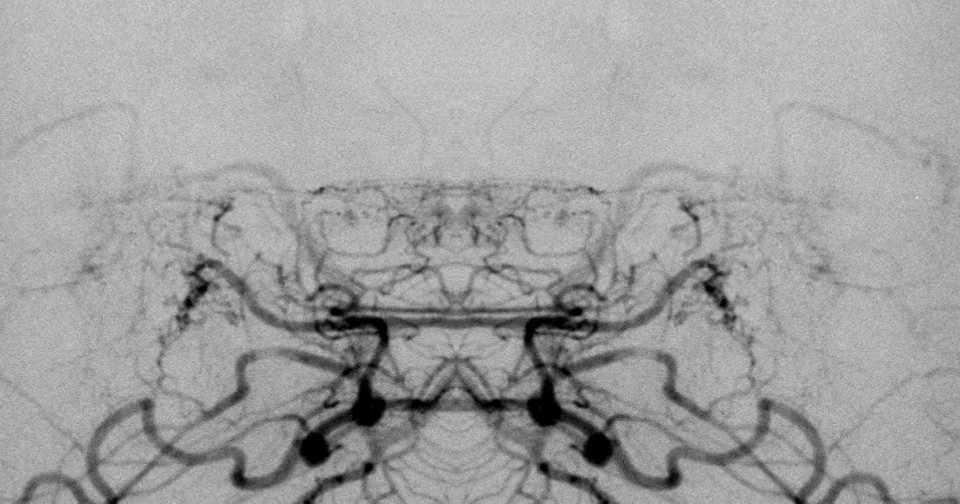

При болезни моямоя наблюдается прогрессирующее нарушение мозгового кровообращения из-за сужения и окклюзии внутренних сонных артерий. В переводе с японского «моямоя» — «клуб дыма». Так описывают сеть коллатеральных сосудов на основании мозга, которая при этом заболевании становится похожа на ангиограмме на легкую дымку. Хотя болезнь считается редкой, она распространена в Восточной Азии: в Корее и Японии заболеваемость составляет 6,0–16,1 на 100 тысяч населения. В основном болезнь моямоя поражает женщин детородного возраста, что повышает риск осложнений во время беременности и родов.